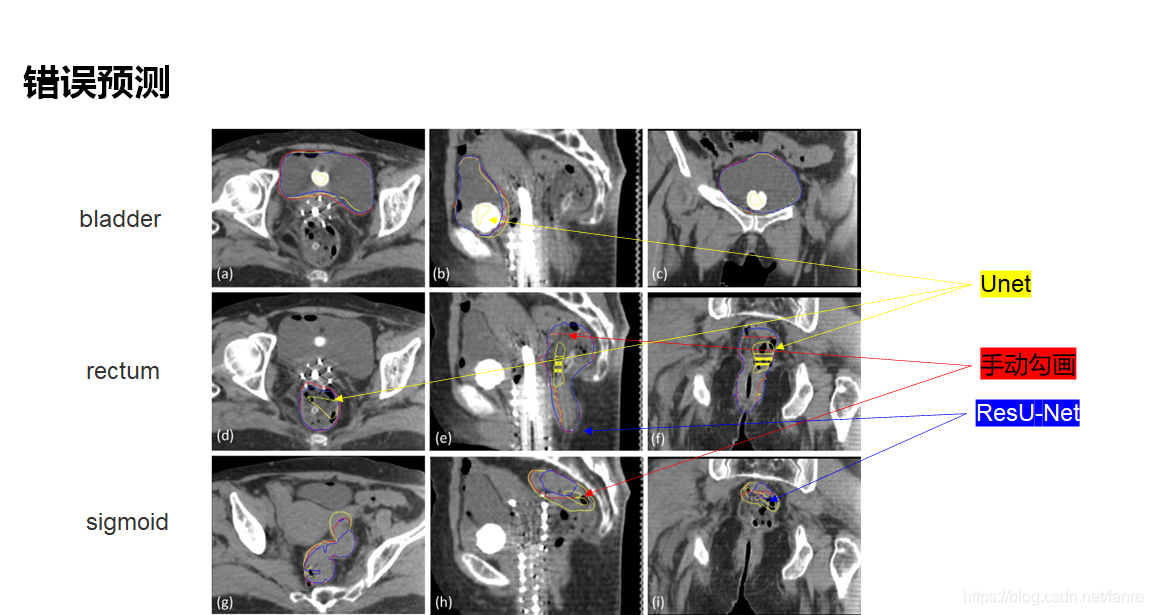

基于深度学习的宫颈癌高剂量率后装放疗危及器官自动勾画

基于深度学习的宫颈癌高剂量率后装放疗危及器官自动勾画